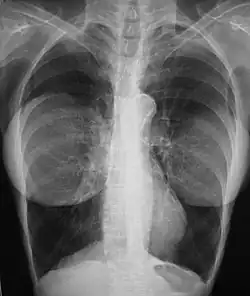

Mamografie

Přítomnost radiologicky neprůhledných prsních implantátů (buď fyziologických, nebo silikonových) může narušit radiografickou citlivost mamografu, to znamená, že na snímku nemusí být vidět žádný přítomný nádor. V takovém případě je pro zjištění přítomnosti nebo nepřítomnosti rakovinného nádoru nutné provést mamografické vyšetření Eklundovým pohledem, při kterém se prsní implantát ručně posune proti hrudní stěně a prs se vytáhne dopředu, aby mamograf mohl zobrazit větší objem vnitřních tkání; přesto zůstává přibližně jedna třetina prsní tkáně nedostatečně zobrazena, což vede ke zvýšené míře mamografických vyšetření s falešně negativními výsledky.[93][94]

Studie rakoviny prsu Cancer in the Augmented Breast: Diagnosis and Prognosis (1993) a Breast Cancer after Augmentation Mammoplasty (2001) u žen s prsními implantáty nezaznamenaly žádné významné rozdíly ve stadiu onemocnění v době diagnózy rakoviny; prognózy jsou u obou skupin žen podobné, přičemž u augmentovaných pacientek je nižší riziko následné recidivy rakoviny nebo úmrtí.[95][96] Naopak se zdá, že použití implantátů k rekonstrukci prsu po mastektomii nemá žádný negativní vliv na výskyt úmrtí v souvislosti s rakovinou.[97] Skutečnost, že u pacientek s prsními implantáty jsou častěji diagnostikovány hmatné – nikoli však větší – nádory, naznačuje, že stejně velké nádory mohou být u augmentovaných pacientek snadněji hmatné, což by mohlo kompenzovat zhoršené mamografické zobrazení.[98] Snadná hmatnost nádoru v prsu je důsledkem ztenčení prsní tkáně kompresí, které je a priori přirozené u menších prsů (protože mají menší objem tkáně), a toho, že implantát slouží jako radiooptický podklad, na jehož pozadí lze rakovinný nádor odlišit.[99]

Prsní implantát nemá žádný klinický vliv na lumpektomickou operaci pro zachování prsu u žen, u nichž se po implantaci vyvinul karcinom prsu, ani neinterferuje s léčbou zevním ozařováním (XRT); navíc je po léčbě běžný výskyt fibrózy prsní tkáně, a tím i zvýšená míra kapsulární kontraktury.[100] Existují předběžné důkazy, že ženy, které podstoupily augmentaci prsou, mají horší prognózu rakoviny prsu.[101] Použití implantátů k rekonstrukci prsu po mastektomii z důvodu rakoviny prsu zřejmě nemá žádný negativní vliv na úmrtí v souvislosti s rakovinou.[97][102]

Bylo hlášeno mnoho případů dalších nežádoucích účinků mamografie u žen s prsními implantáty; většinu těchto případů tvoří prasknutí v důsledku tlaku působícího na prsní implantát.[103] Komprese může také vést k bolesti nebo zhoršit již existující bolest v prsou.[103]